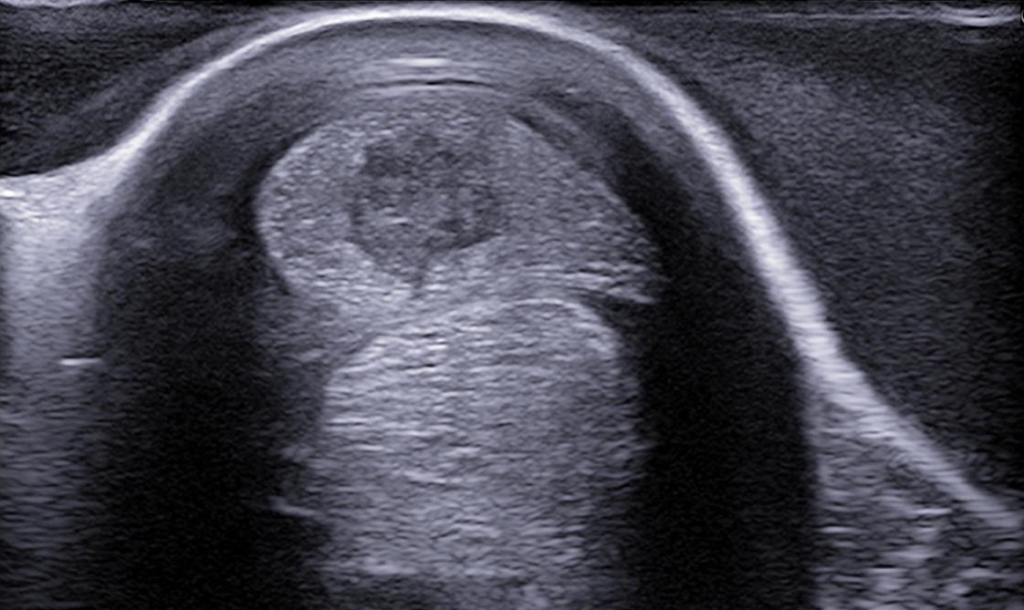

Doordat bot heel slecht geluidsgolven doorlaat is met een echografisch onderzoek niet mogelijk door benige delen heen te kijken. Wel is het met de echo mogelijk om heel gedetailleerd het buitenste laagje van het bot in beeld te brengen. Dit kan zeer nuttig zijn bij bijvoorbeeld schiefels of kraakbeen veranderingen aan de rand van het gewricht. Ook kunnen we met behulp van het echoapparaat de gewrichtsholtes scannen op bloedingen, overvullingen of chronische veranderingen.

Een peesblessure kan op verschillende manieren tonen bij een peesscan. Meestal is er bij een grote recente blessure sprake van zwelling rondom de pees en is de pees zelf ook toegenomen in omvang. Met name blessures in het hart van de pees zijn vaak zichtbaar als een donkere holte in het midden van de pees. Als we een beschadigde pees in de lengte richting bekijken dan valt op dat er een donkere strook, zonder vezelbanen, in de pees aanwezig is.